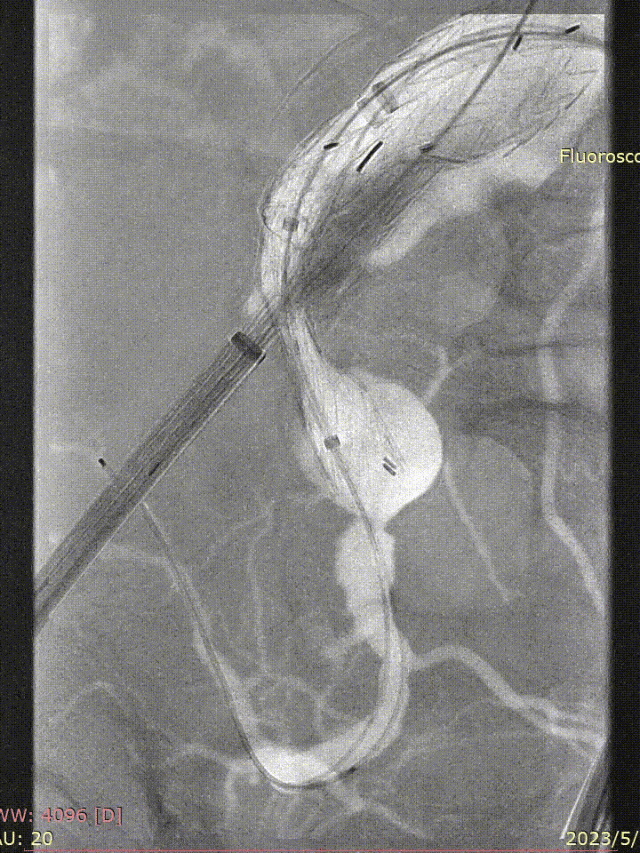

术前情况:74岁男性,肾下腹主动脉瘤,瘤体最大直径66mm,累及双侧髂总,右侧髂内扩张伴开口狭窄,左侧髂内夹层。

手术过程:根据患者及家属要求保双侧髂内,遂计划双侧髂内重建,右侧优先,左侧髂内情况尝试开通。手术中,先进行造影和翻山建立通路。

IBE主体就位与右侧髂内重建

随后IBE主体就位,释放主体并翻山DSF鞘至短腿确认髂内情况,确认髂内健康锚定区情况及长度测量,释放髂内分支。对髂内支架狭窄处扩张,输送和释放第二枚髂内分支并手推造影确认通畅,IBE主体及各连接处后扩。

左侧髂内动脉超选与重建

右侧髂内动脉重建完成后,建立对侧翻山通路,再次确认主体位置及左侧髂内动脉情况。左侧髂内超选困难,经反复确认导丝配合导管超选真腔,手推造影确认髂内情况后释放远端VB,释放左侧髂内分支HGB并确认通畅情况。最后按常规EVAR置入腹主动脉支架主体,超选入主体短腿内对接IBE主体释放桥接喇叭腿。

左侧髂内分支HGB释放

手推造影确认通畅情况

术后情况:造影提示动脉瘤完全隔绝,手术成功实现了保留双侧髂内动脉并隔绝动脉瘤的目标,患者病情得到有效控制。

术后造影